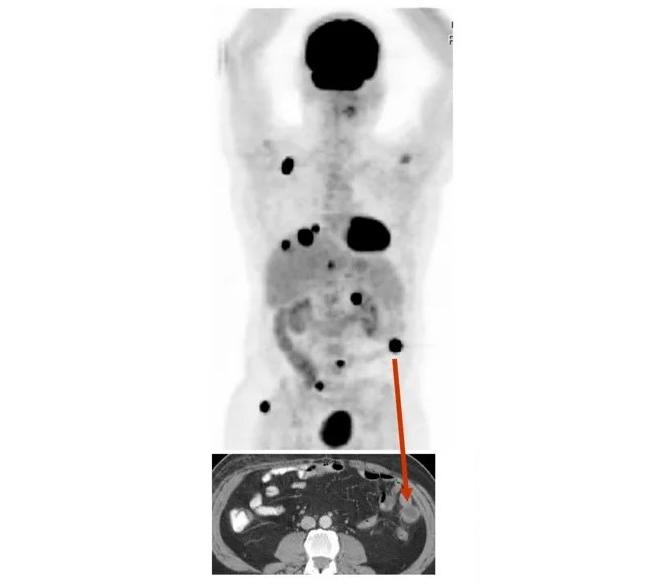

PET/CT scan of a patient with metastatic melanoma.

Credit: Credit: J Transl Med. March 2008. https://doi.org/10.1186/1479-5876-6-12. CC BY 4.0.